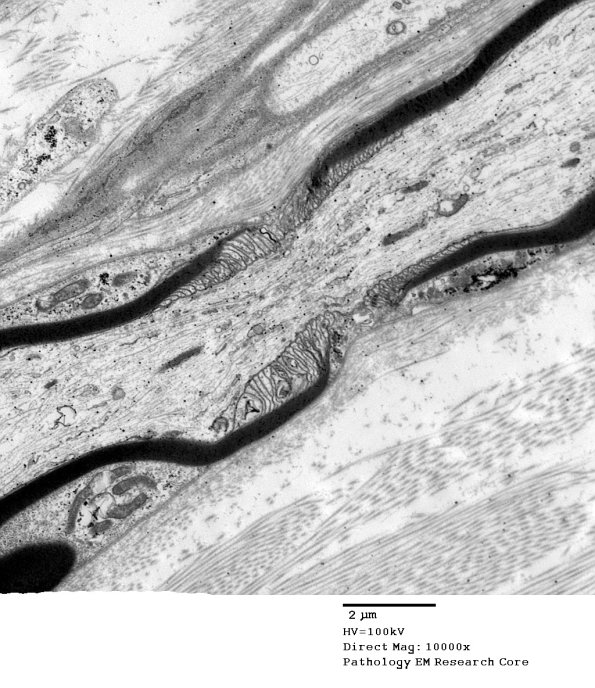

10A4,5 Intra-axonal accumulation of organelles and constriction of axonal dimensions at the node. (electron micrographs)